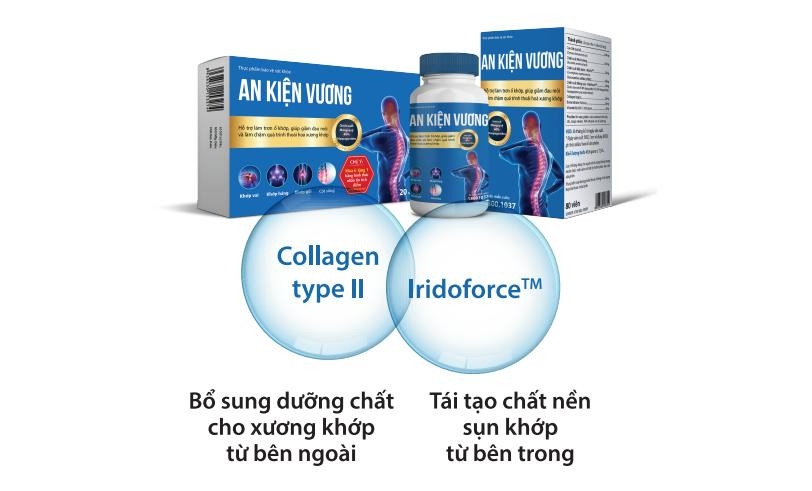

Ngoài IridoforceTM - chiết xuất Móng quỷ với hàm lượng hoạt chất cao, An Kiện Vương còn chứa Collagen type II, giúp mang đến cơ chế toàn diện, vừa bổ sung từ bên ngoài, vừa tái tạo chất nền sụn khớp từ bên trong. Tác dụng này đã được nghiên cứu và chứng minh nên người bệnh có thể yên tâm lựa chọn.

Chính vì thế, An Kiện Vương giúp giải quyết được nguyên nhân sâu xa gây đau nhức và thoái hoá xương khớp, do vậy mang lại hiệu quả cao và bền vững.

| An Kiện Vương vừa bổ sung dưỡng chất cho xương khớp từ bên ngoài, tái tạo chất nền sụn khớp từ bên trong |